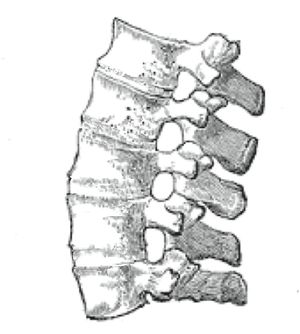

| An ankylosing spine in which the vertebrae become fused together. | |

التهاب الفقار المقسط أو اللاصق Ankylosing spondylitis باليونانيةankylos, stiff; spondylos, vertebrae), تسمى قديماًBekhterev's disease, Bekhterev syndrome, و Marie-Strümpell disease هو نوع من التهاب المفصل في العمود الفقري. وهو يسبب تورماً بين الفقرات، والفقرات هي الأجزاء الأسطوانية التي تكون العمود الفقري، كما يسبب تورماً في المفاصل بين العمود الفقري والحوض. إن التهاب الفقار المقسط أو اللاصق هو أحد أمراض المناعة الذاتية. إن الجهاز المناعي المسؤول عن حماية الجسم من العدوى يقوم بمهاجمة أنسجة الجسم نفسها في حالة أمراض المناعة الذاتية. ويكون التهاب الفقار اللاصق أكثر انتشاراً وخطورة عند الرجال. وكثيراً ما يكون مرضاً ينتقل عن طريق الوراثة.[1]

يبدأ التهاب الفقار المقسط في صغار البالغين بألم مبهم في أسفل الظهر، ويبوسة مديدة تالية للراحة تتحسن جزئياً بالحركة والتمارين الرياضية. ينتشر الألم إلى الاليتين والقسم الخلقي من الساقين. كما يحدث ألم في القفص الصدري بإصابة المفاصل الغضروفية المركزية فيه، وقد يكون لهذا الألم صفات جنبية، ويظهر الألم أيضاً في مفاصل قبضة القص Manubriosternal والمفاصل القصية الترقوية. إن التهاب ارتكازات الأربطة والأوتار عرض بارز وقد يكون العرض الأول. وينجم الألم عن التهاب الأصابع Dactylitis ' أو وتر أشيل، أو اللفافة الأخمصية، أو عرف الحرقفة iac أ I Crest. تكون الإصابة المفصلية بشكل الام مفصلية، أو التهاب مفاصل عديد، يصيب المفاصل الزليلة الدانية وبشكل غير متناظر كالكتفين والمرفقين والركبتين ونادرا المفاصل الصغيرة القاصية. وتترافق هذه الإصابة بيبوسة صباحية مديدة وأحياناً بتورم الا أنه من غير الشائع حدوث إصابة مفصلية تاكلية شديدة.